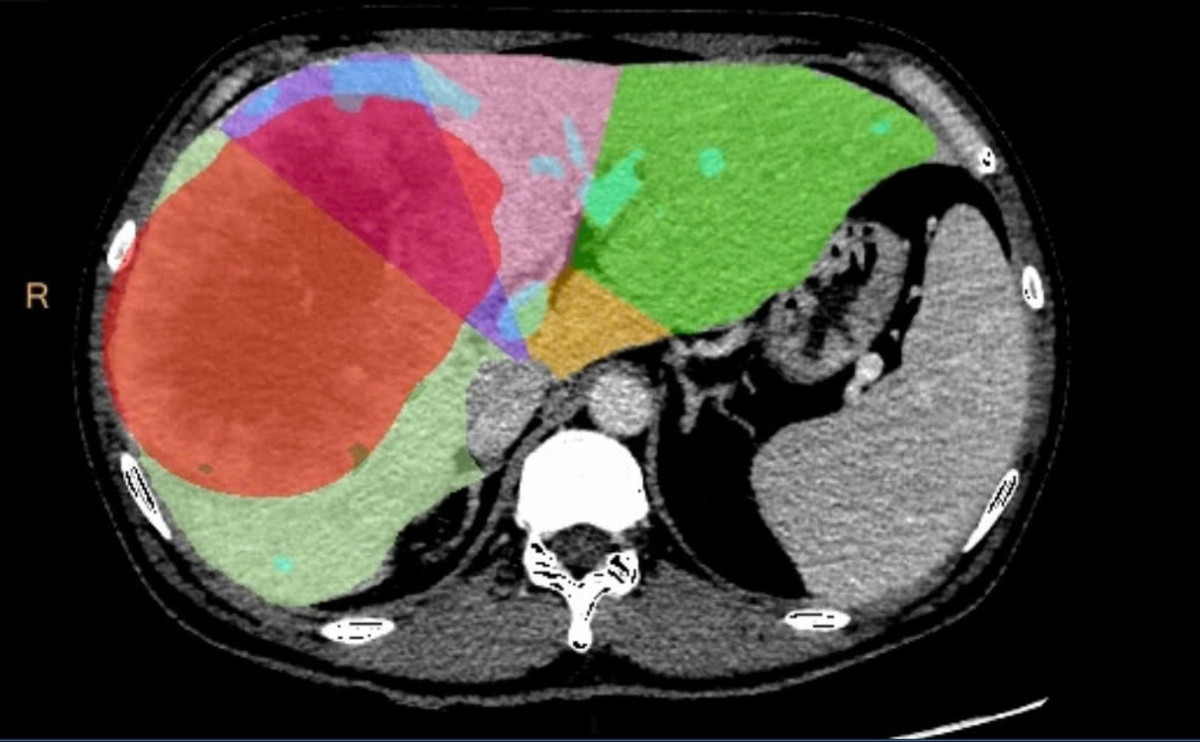

Tại thời điểm nhập viện vào tháng 7/2025, thể tích gan trái chỉ chiếm 27,1% tổng thể tích gan, chưa đủ an toàn cho phẫu thuật cắt bỏ phần gan phải mang khối u.

Gan phải và khối u giảm kích, phần gan trái lành phát triển phì đại - Ảnh BVCC

Ở giai đoạn hai, ê kíp phẫu thuật đã thực hiện cắt bỏ toàn bộ gan phải mang khối u, với khối lượng hơn 1,5 kg. Ca mổ thành công, bệnh nhân hồi phục tốt và không gặp biến chứng suy gan do thiếu hụt thể tích gan chức năng.